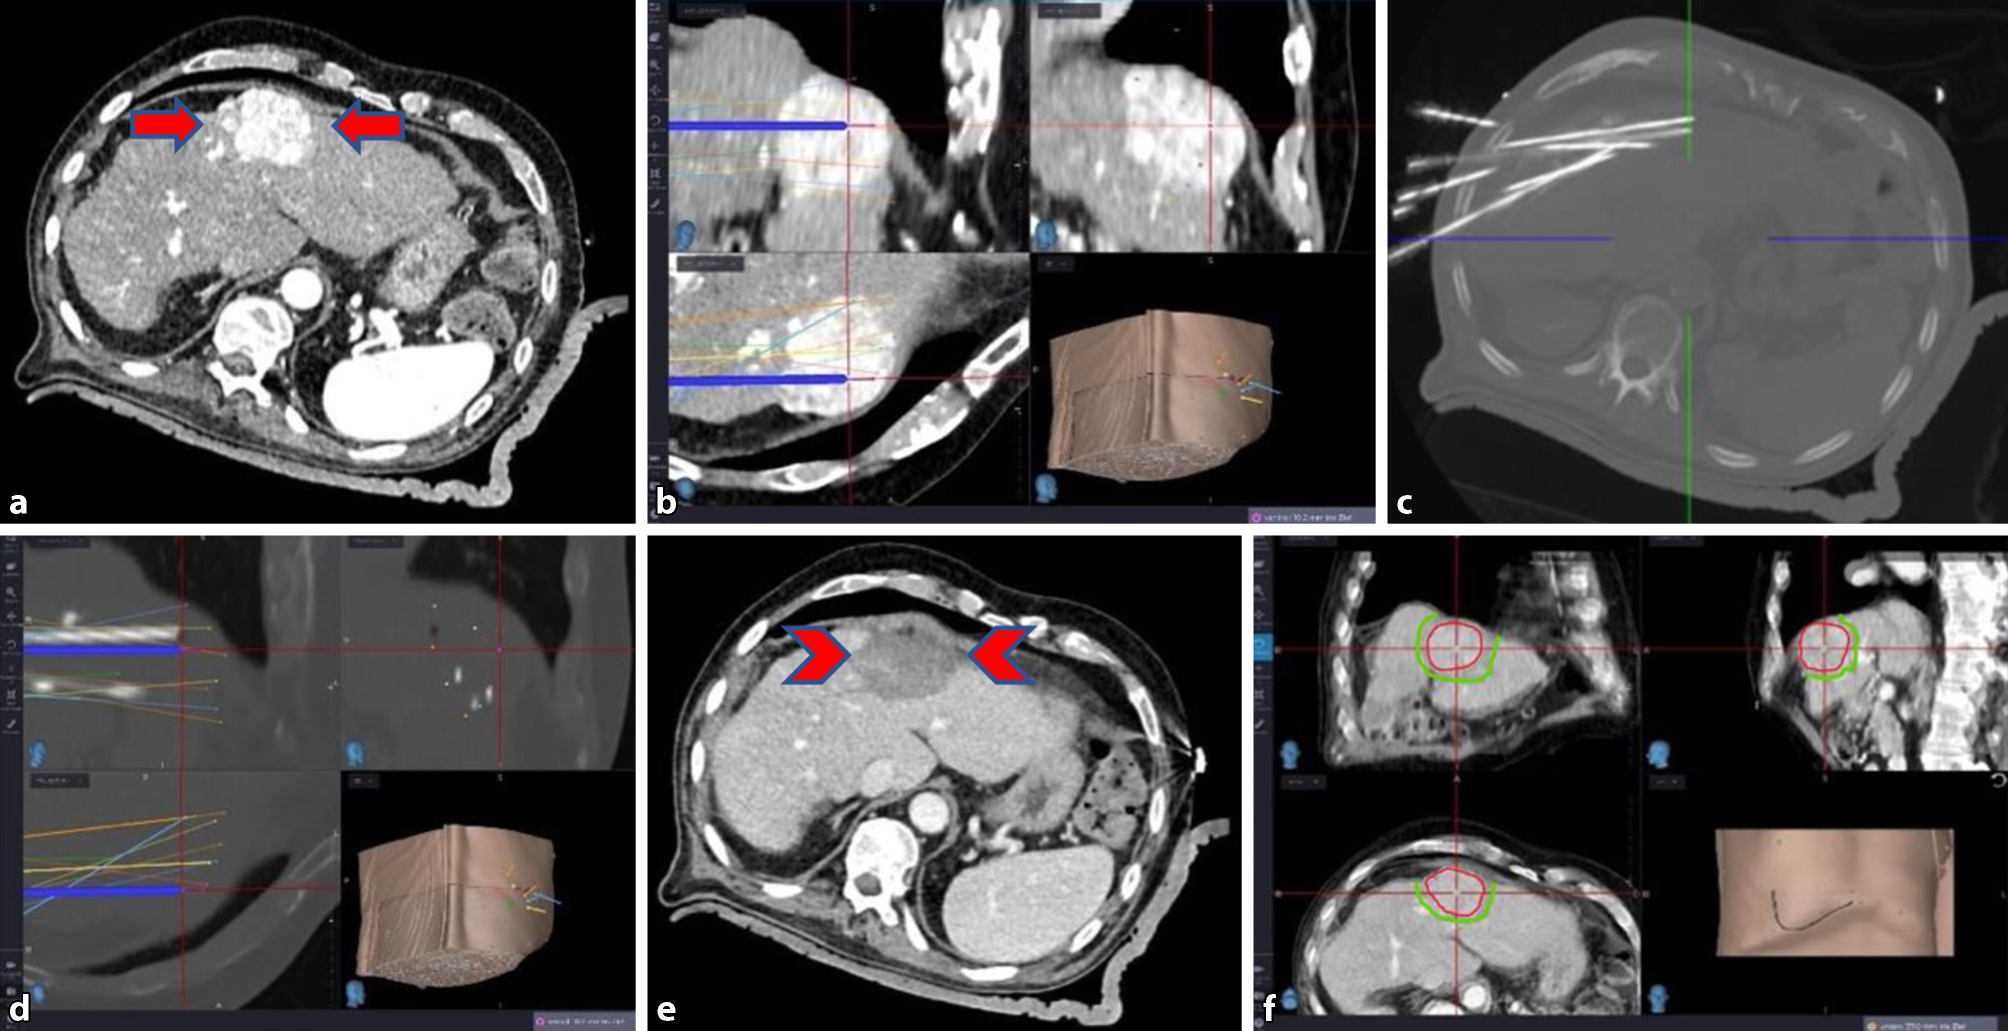

The stereotactic three-dimensional approach for thermal ablation planning allows the implementation of several overlapping ablation zones in order to achieve a sufficient three-dimensional safety margin. A targeting device is used to place several needles accurately and reproducibly [20] under general anesthesia and muscle relaxation. Image fusion of preoperative and intraoperative images allows for immediate intraoperative verification of a sufficient ablation zone overlapping the tumor ([2125]; Fig. 1).

Fig. 1

Stereotactic thermal ablation (SRFA) in a 76-year-old man with history of fatty liver disease and liver cirrhosis and hepatocellular carcinoma (HCC). a Contrast-enhanced CT depicting a 52 mm HCC in segment IV (arrows). b Planning of multiple needle trajectories. c Maximum intensity projection (MIP) of native control CT with coaxial needles in place. d Image fusion of needle control CT with planning CT (with the planned trajectories) confirms precise needle placement. e Intraoperative contrast-enhanced CT immediately after radiofrequency ablation (RFA) showing devascularized ablation zone (arrowheads). Image f is showing the control CT with the ablation necrosis at the end of the procedure, which is fused to the arterial phase planning CT in imageaI to prove overlap of the tumor (red line) and the ablation zone (hypodenserim), confirming the ablation margin (green line)